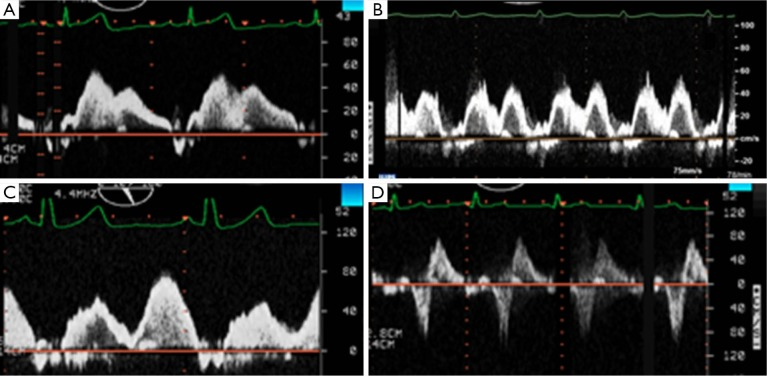

肺静脉血流(图23) |

图23二尖瓣返流的肺静脉频谱:A无反流B轻度反流C中度反流D重度反流

引自:Ann Cardiothorac Surg. Nov 2013; 2(6): 796–802.